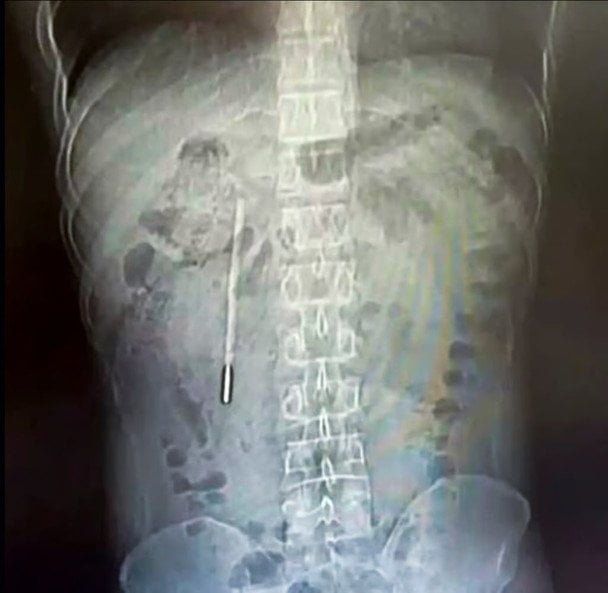

Сканування, проведене у Першій афілійованій лікарні Веньчжоуського медичного університету, підтвердило наявність стороннього предмета у дванадцятипалій кишці. Фахівці наголосили на критичності ситуації: кінчик термометра притискався до стінки кишечника, що загрожувало перфорацією та масштабною внутрішньою кровотечею.

Хірургічне втручання тривало 20 хвилин. Складність операції полягала в тому, що крихкий предмет знаходився поруч із жовчними протоками. Лікарям вдалося вилучити термометр цілим — ртуть не потрапила в організм, хоча позначки на склі за цей час майже повністю вицвіли.

У Китаї з тіла чоловіка вилучили ртутний термометр. / © Weibo